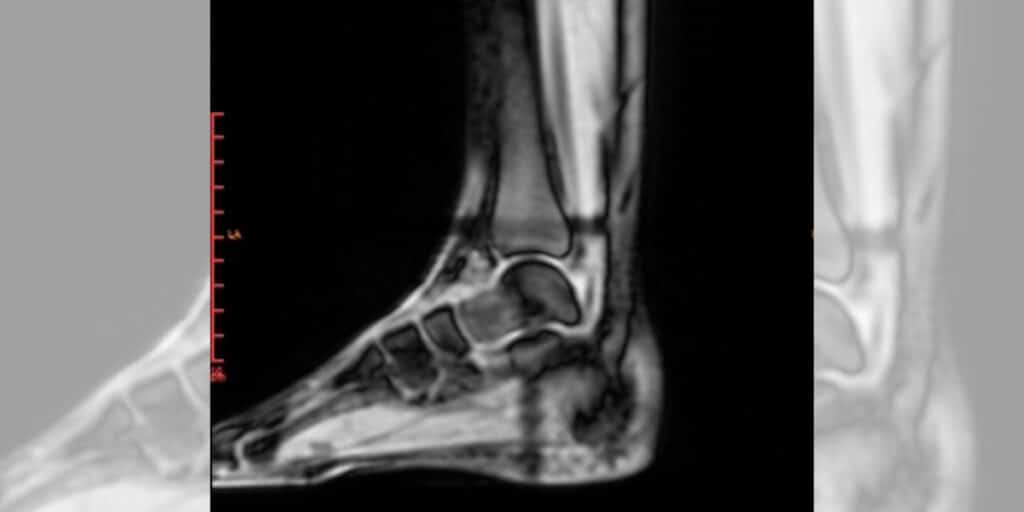

The amount of recovery and healing time required is dependent on progression of the BSI, location, grade of reaction (grades 1-4), and quality of blood supply to the affected bone. Most bone stress injuries experienced by runners tend to occur in the feet, ankle, bones of the lower limbs, and pelvis. Bone stress injuries to areas such as the femoral neck, talus and navicular may take the longest to heal and carry the most risk of complication due to delayed union resulting from decreased blood supply in the area. Immediate fractures caused by trauma to the area may be categorized as a displaced, non-displaced, or compound fracture and may require immobilization of the bone and/or surgery. The treatment for non-complicated stress injuries and fractures is often straight forward with modification to the amount of weight bearing on the bone which includes a period of rest to the bone and gradual return to sport. Addressing any physical root causes that led to the compromised integrity of the bone can be more nuanced.